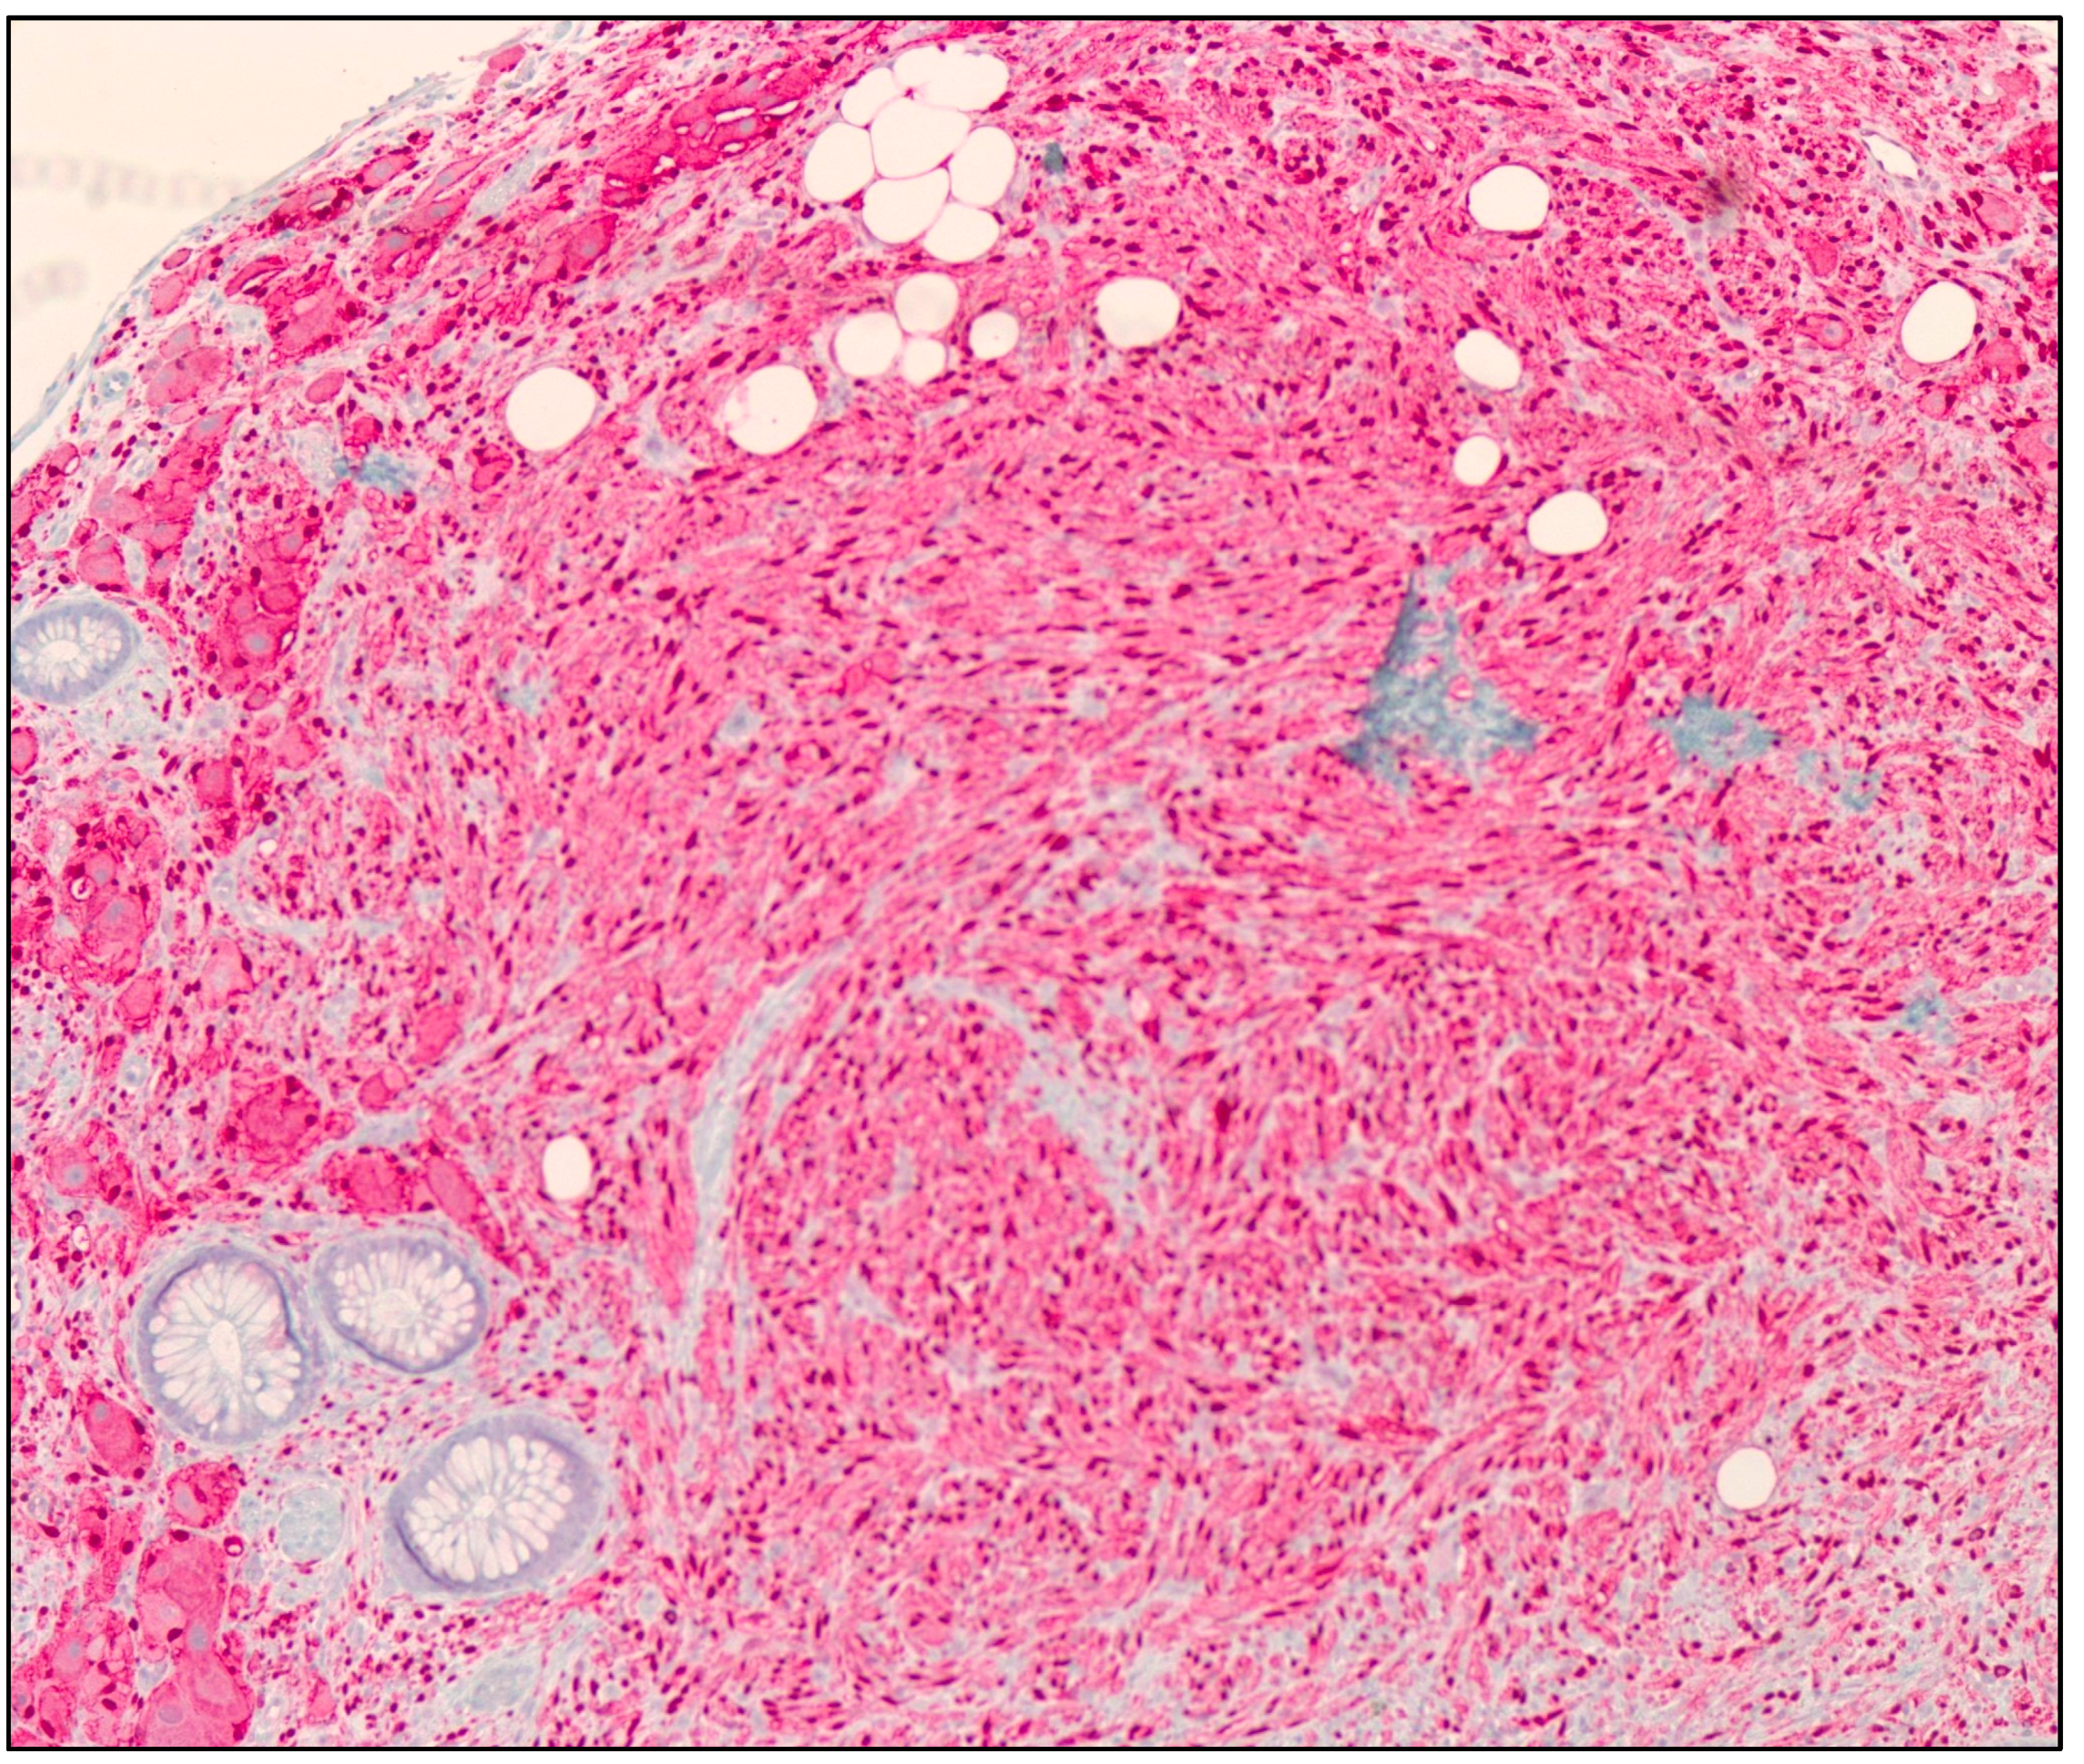

Due to their rarity, the incidence of GNs is not exactly known. Based on our recent literature review, we suspect that there are less than 100 documented cases of colonic GN, and less than 5 cases in animals with colonic GNs. Immunohistochemistry (IHC) is often used as a method to detect the specific protein markers, which help with the diagnosis of colonic GNs. Histologically, GNs reveal mature ganglion cells that are large with axons, Schwann cells, fibrous stroma, and satellite cells (Figure 1). IHC of these lesions may display positivity with neurofilaments, synaptophysin (Figure 2), chromogranin, S100 protein (Figure 3), glial fibrillary acidic protein (GFAP), and CD56 in ganglion and Schwann cells [9]. To the best of our knowledge, our study presents the biggest published case series and review of the literature conducted to date.

Figure 1.

Hematoxylin and eosin (H&E) microscopic image of a ganglioneuroma. The image shows proliferation of spindle cells with wavy nuclei (Schwann cells, black arrow) and scattered large cells with eccentric vesicular nuclei, prominent nucleoli, and abundant amphophilic cytoplasm (Ganglion cells, red arrow) (100× magnification).